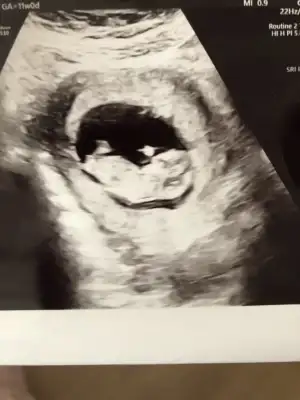

Erkeğim diye bağırıyorMerhabaaa bendee tahminn alablrmym![]()

Doktorum da ilk böyle dedi pazartesi gttim kıza benzettim dediErkeğim diye bağırıyor![]()

Kız gibi sanki daha önceki karanlık USG emin olmamıştımBen bugün gene kontroldeydimIkra meyra her seferin farklı tahminde bulunuyor ama bugün met ve emin söyledi. Bakalım sen ne diyeceksin? Bemce poposu dönük ama öyle bişey demedi.